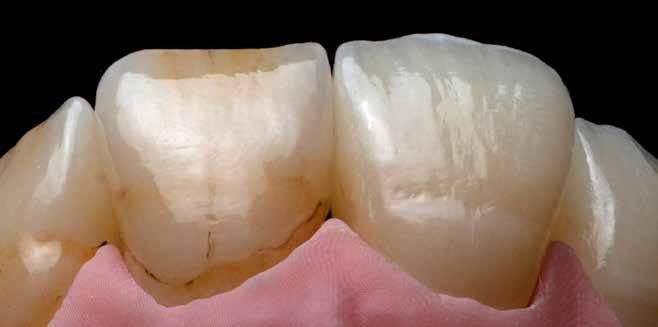

MED. DENT Abradált frontfogakkal rendelkező felnőtt páciens interdiszciplináris kezelése

2–4. képek: Festett példák.